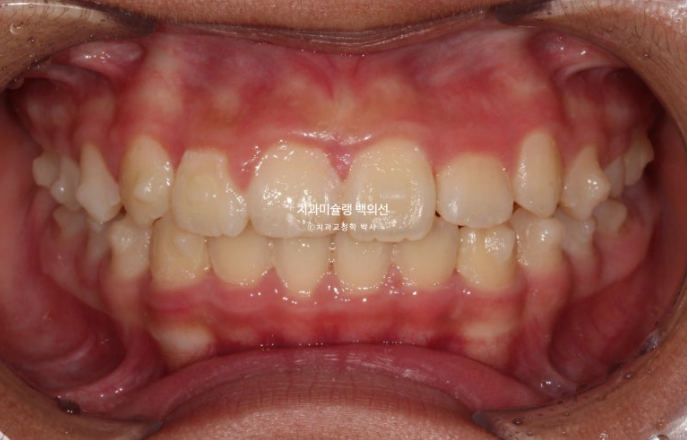

24년 1월 교정치료를 위해 온 만 10세 어린이 입니다.

3년 전에 소아치과에서 앞니 부분교정을 한 적이 있다고 합니다.

그래서 위 앞니에는 중절치 두 개를 잇는 철사유지장치가 붙어있었습니다.

중심선이 약 2mm 어긋나 있으며 위 앞니 치축은 한쪽으로 기울어져 있습니다.

앞니가 깊게 물리는 과개교합도 보입니다.

24.02

공간부족으로 인한 덧니가 심해 반대교합이 있습니다.